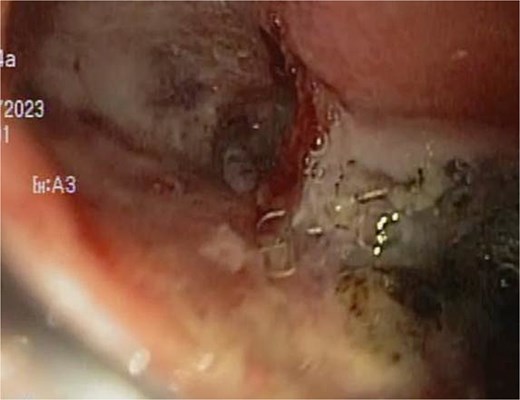

A 44-year-old female with no significant medical history underwent Roux-en-Y gastric bypass for grade III obesity (BMI 41). She presented with necrosis of the gastric pouch within the first 48 hours, leading to leakage of the gastrojejunal and jejunojejunal anastomoses. Esophagojejunal anastomosis and revision of the jejunojejunal anastomosis were performed, but the patient developed septic shock due to esophagojejunal anastomosis leakage, requiring 7 days in intensive care. Upon stabilization, she was referred to our service for endoscopic management of an esophagojejunal fistula. A 10 mm fistulous orifice was observed (Fig. 1), and EVAC therapy was initiated using a polyurethane sponge with an 8 Fr catheter at 125 mmHg continuous suction (Fig. 2). Six changes were made at 3–5-day intervals.

The placement of the catheter and sponge for EVAC therapy is observed.